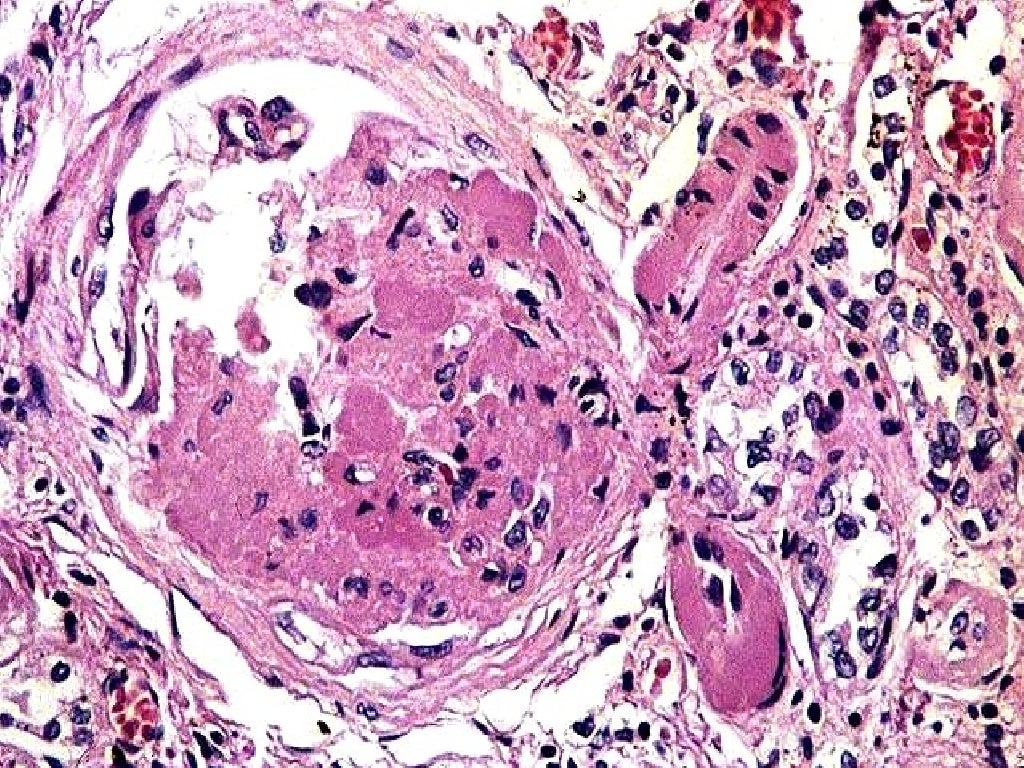

Introducción a los trastornos vasculares renales Trastornos renales y